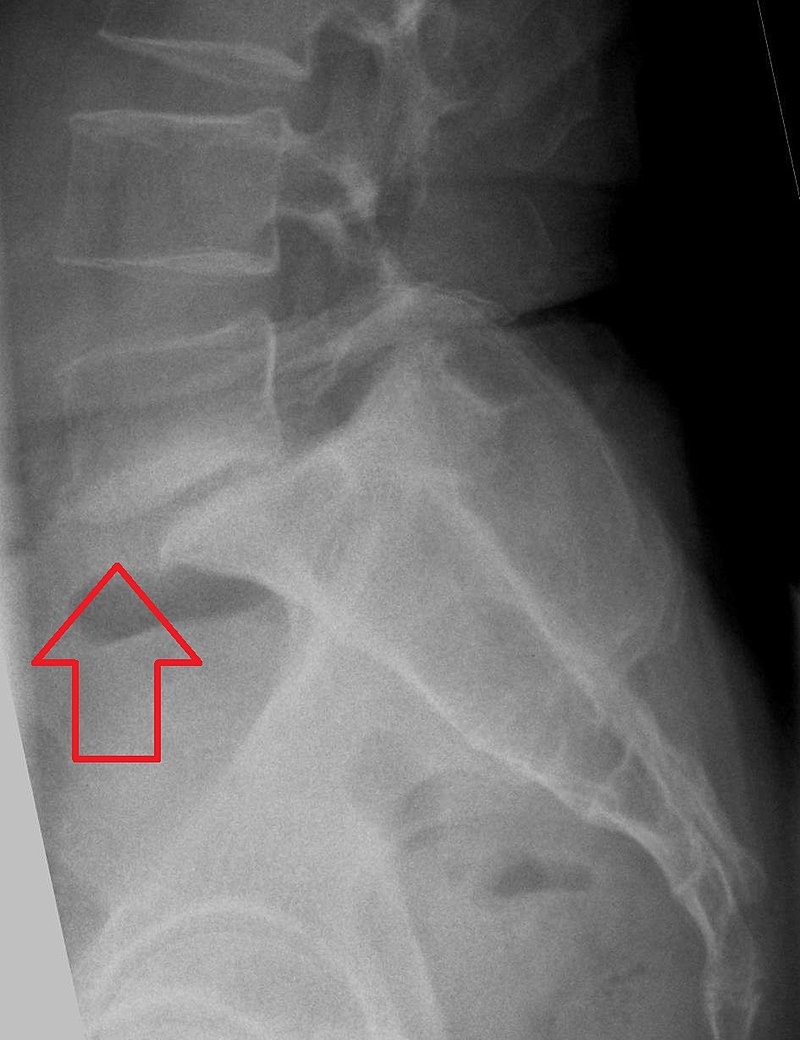

척추전방전위증의 엑스레이(x-ray) 촬영 이미지